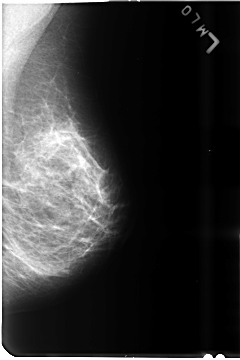

B_3491_1.LEFT_MLO

LEFT_MLO LINES 4672 PIXELS_PER_LINE 3112 BITS_PER_PIXEL 12 RESOLUTION 50 NON_OVERLAY